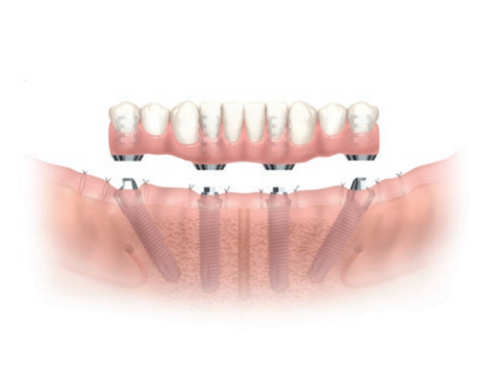

- Fixed Implant Dentures: Often referred to as ProArch or All-on-4, unlike removable implant dentures, the denture is permanently fixed to the implant posts and can only be removed by your dentist.

Fixed Dentures

All-on-4 or ProArch + Fixed Denture

2. ProArch (All-on-4) Fixed Dentures

ProArch is Straumann’s treatment concept for immediate temporary restorations in edentulous patients. Whilst All-on-4 is Nobel Biocare’s tradename treatment concept for its immediate function fixed dentures. Straumann and Nobel Biocare are established global implant brands that has been manufacturing and producing implants for over 30 to 50 years*

The treatment concept is designed specifically for full-arch rehabilitation. And unlike traditional methods, this immediate concept combines the surgical and restorative phases into a single treatment phase period. Fixed provisional dentures are attached to the implants posts within days of the surgical surgery. By tilting the posterior implants, available dense bone typically in the anterior jaw is used to hold the implant post that often assists in eliminating the need for complex bone grafting at the posterior area. ProArch or All-on-4 is a solution option for patients with posterior bone loss.

2. TEETH EXTRACTIONS & IMPLANT PLACEMENT

During the surgical visit, remaining teeth are extracted and the dental implant posts is embedded into the jaw bone. Your dentist may take the impression during the same surgical placement visit or shortly after implant placement (within 1 to 3 days when bleeding has stopped) to send off to the dental lab for your fixed dentures to be constructed.

3. CONSTRUCT AND ADJUSTMENT OF DENTURES

On delivery of the dentures framework, it is tried on. Teeth will then be added onto the framework. You may require several adjustments visits before your dentists fully completes a comfortable and correct fit. Once the hybrid denture is properly made, it is secured into position with screws.